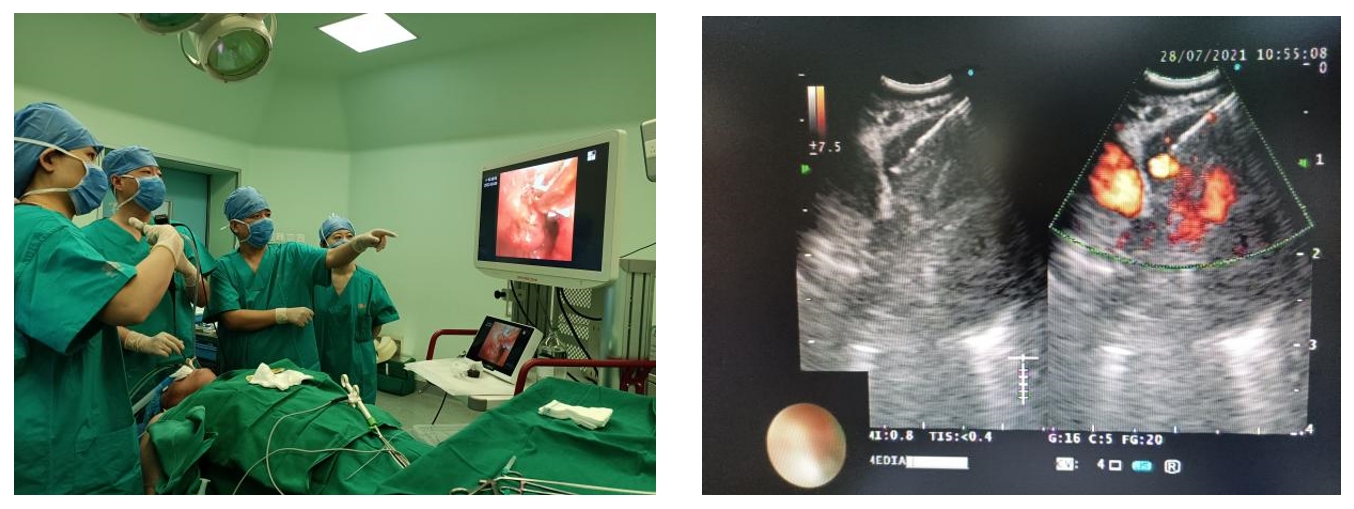

呼吸与危重症医学部呼吸内镜诊疗中心成立于2020年5月,目前已成为国内技术水平领先的呼吸介入单位之一,开展了多项呼吸内镜介入技术,如EBUS-TBNA、硬质支气管镜、气道支架置入、氩等离子凝固术、冷冻、激光、电磁导航支气管镜等,目前年操作量约为1500余例次。

中心成立以来,开展了全军首例预防性血管介入栓塞+经硬质支气管镜大气道肿瘤切除+超声支气管镜引导纵纵膈肿瘤粒子植入和ECMO辅助大气道肿瘤切除术等高难度手术,为危重患者后续的全身治疗争取了宝贵时间。